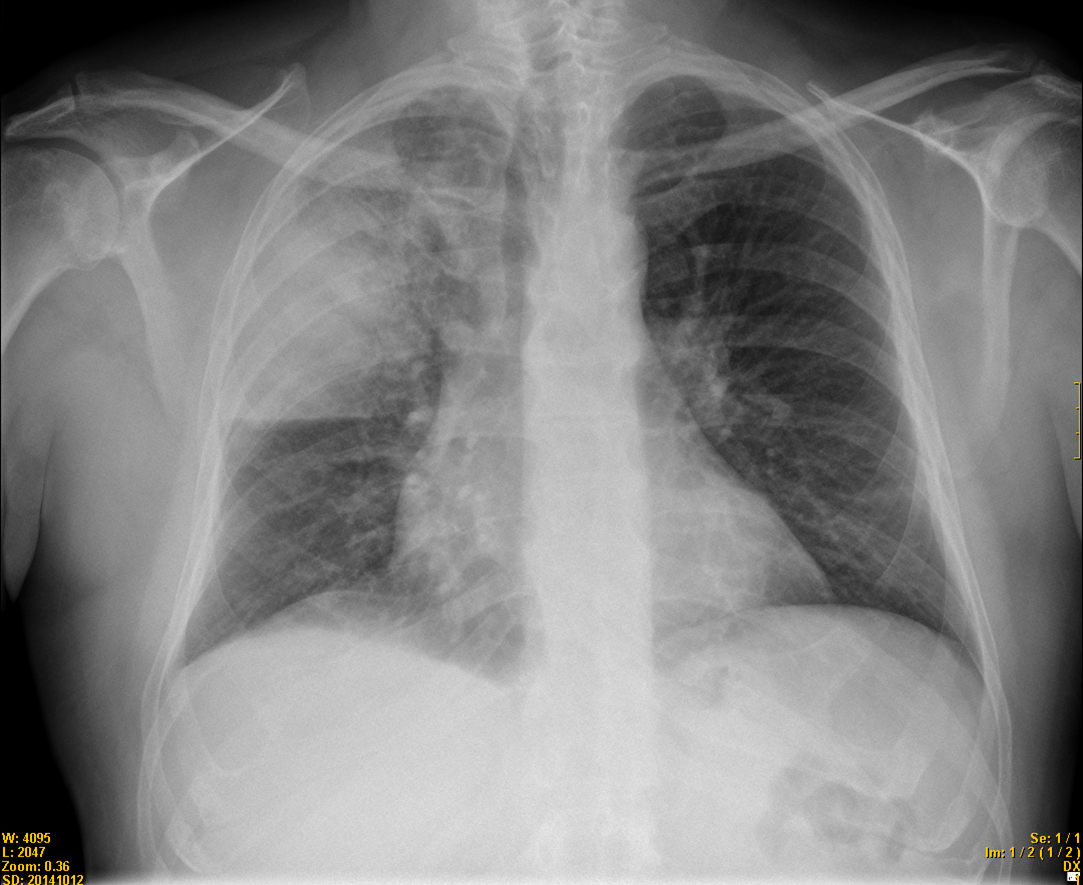

Es fa partint de la història clínica del pacient (edat, patologia prèvia, temps d’evolució i tipus dels símptomes), auscultació, radiografia de tòrax i pràctica de cultius de sang i esput per identificar l’organisme causant.

Radiografia de tòrax, cultius de sang i d’esput o secrecions respiratòries i determinació d’antígens a l’orina.